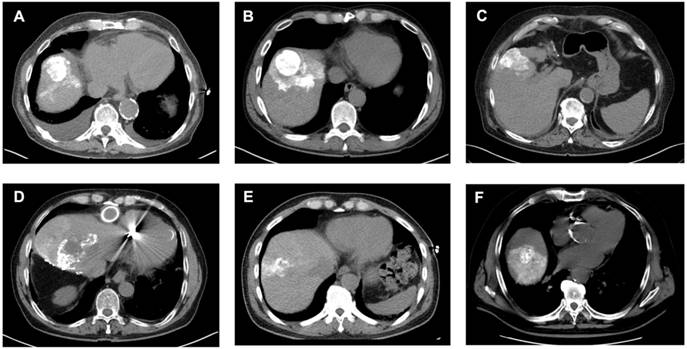

Figure 4

Analysis of Lipiodol Deposition and Distribution Patterns post-cTACE. Legend: CT scans obtained 24 hours after cTACE show different patterns of Lipiodol deposition within target tumors. Homogeneous deposition (A-C) was defined as ≥85% of the tumor volume containing medium or high-density Lipiodol. Heterogeneous deposition (D-F) was defined as <85% intratumoral Lipiodol uptake, characterized by patchy, irregular, or incomplete filling of the tumor. Lipiodol distribution was classified as confined to the tumor, without visible extension into the surrounding liver parenchyma (i.e., A), extending into one adjacent liver segment, without extension into additional segments (i.e., B, E, F), or extending beyond the tumor-bearing segment into at least one adjacent liver segment (i.e., D).

However, when patients were stratified according to Lipiodol distribution, baseline serum IL-6 was significantly elevated in patients with tumoral compared to the segmental Lipiodol distribution (3.75 ± 0.73 pg/mL vs. 2.37 ± 0.65 pg/mL, p = 0.0033). In post-cTACE serum, IL-10, IL-4, TNF-α, and IL-5 were significantly higher in the tumoral group compared to the “segmental” group (IL-10: 2.1 ± 1.07 pg/mL vs. 0.41 ± 0.07 pg/mL, p = 0.0006; IL-4: 0.016 ± 0.003 pg/mL vs. 0.008 ± 0.004 pg/mL, p = 0.0018; TNF-α: 1.93 ± 0.28 pg/mL vs. 1.27 ± 0.13 pg/mL, p = 0.0197; IL-5: 0.97 ± 0.64 pg/mL vs. 0.24 ± 0.06 pg/mL, p = 0.0375). Post-cTACE TIF cytokine analysis revealed no statistically significant differences between patients with tumoral and segmental Lipiodol distribution, respectively. Full data is provided in Supplementary Table S11. Representative imaging examples illustrating Lipiodol deposition and distribution patterns are shown in Figure 4. The associations between Lipiodol deposition and distribution patterns and post-cTACE serum cytokine levels are summarized in Figure 5.